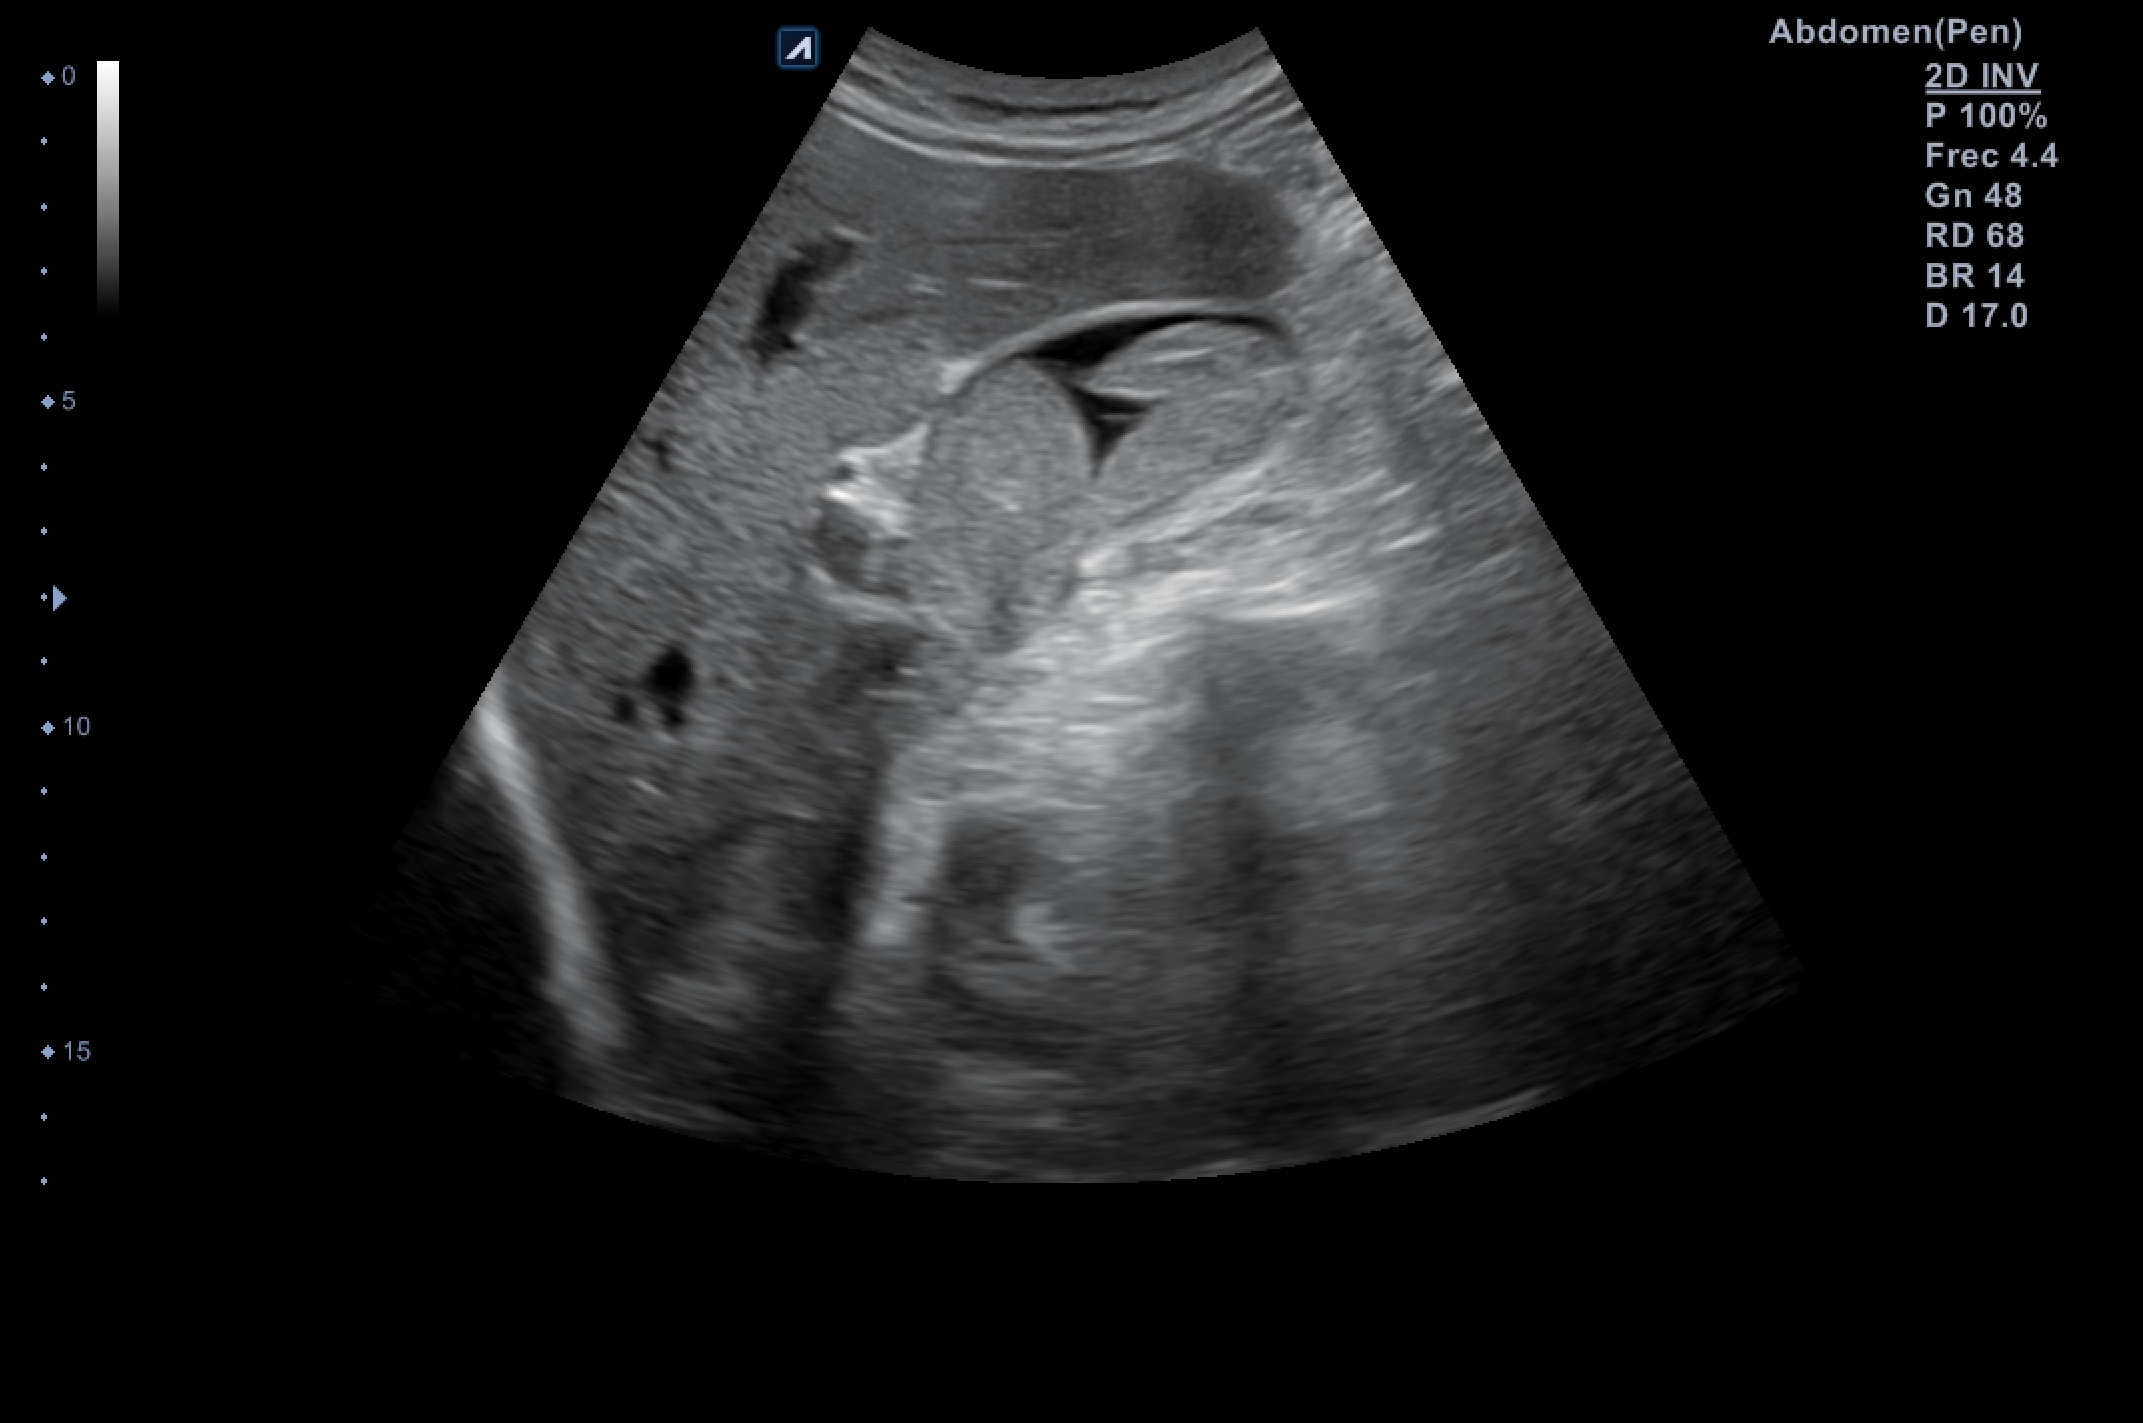

Ecografía abdominal dónde destaca vesícula biliar de pared fina (hasta 3,4 milímetros en su punto de mayor grosor) sin colecciones perivesiculares, que alberga en su interior imagen polilobulada sólida de efecto masa dependiente de su pared posterolateral e inferior que ocupa más de la mitad de la luz, sin captación de flujo Doppler, sugerente de polipoidea o tumoral, de unos 6 x 5 x 3 centímetros de dimensiones mayores.